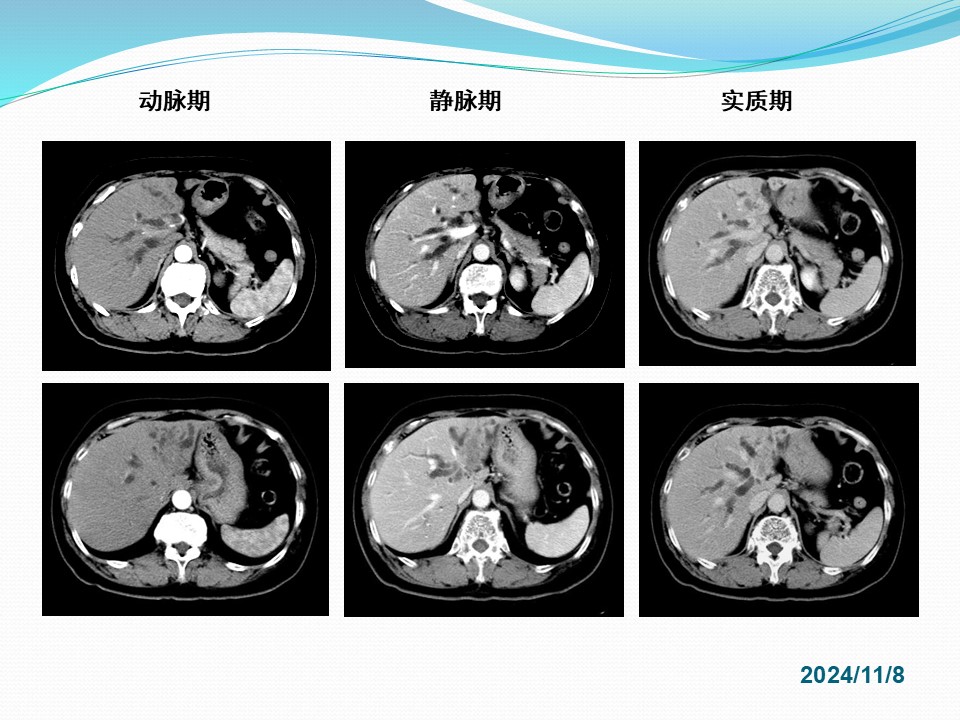

胆管癌外科治疗的实践和存在问题的探讨

Biliary duct cancer / Cholangiocarcinoma

定义:发生于肝外胆管(含左右肝管主干至胆总管下端)恶性肿瘤的总称。不包括肝内胆管癌、肝脏胆管细胞癌、胆囊癌、乏特壶腹癌。